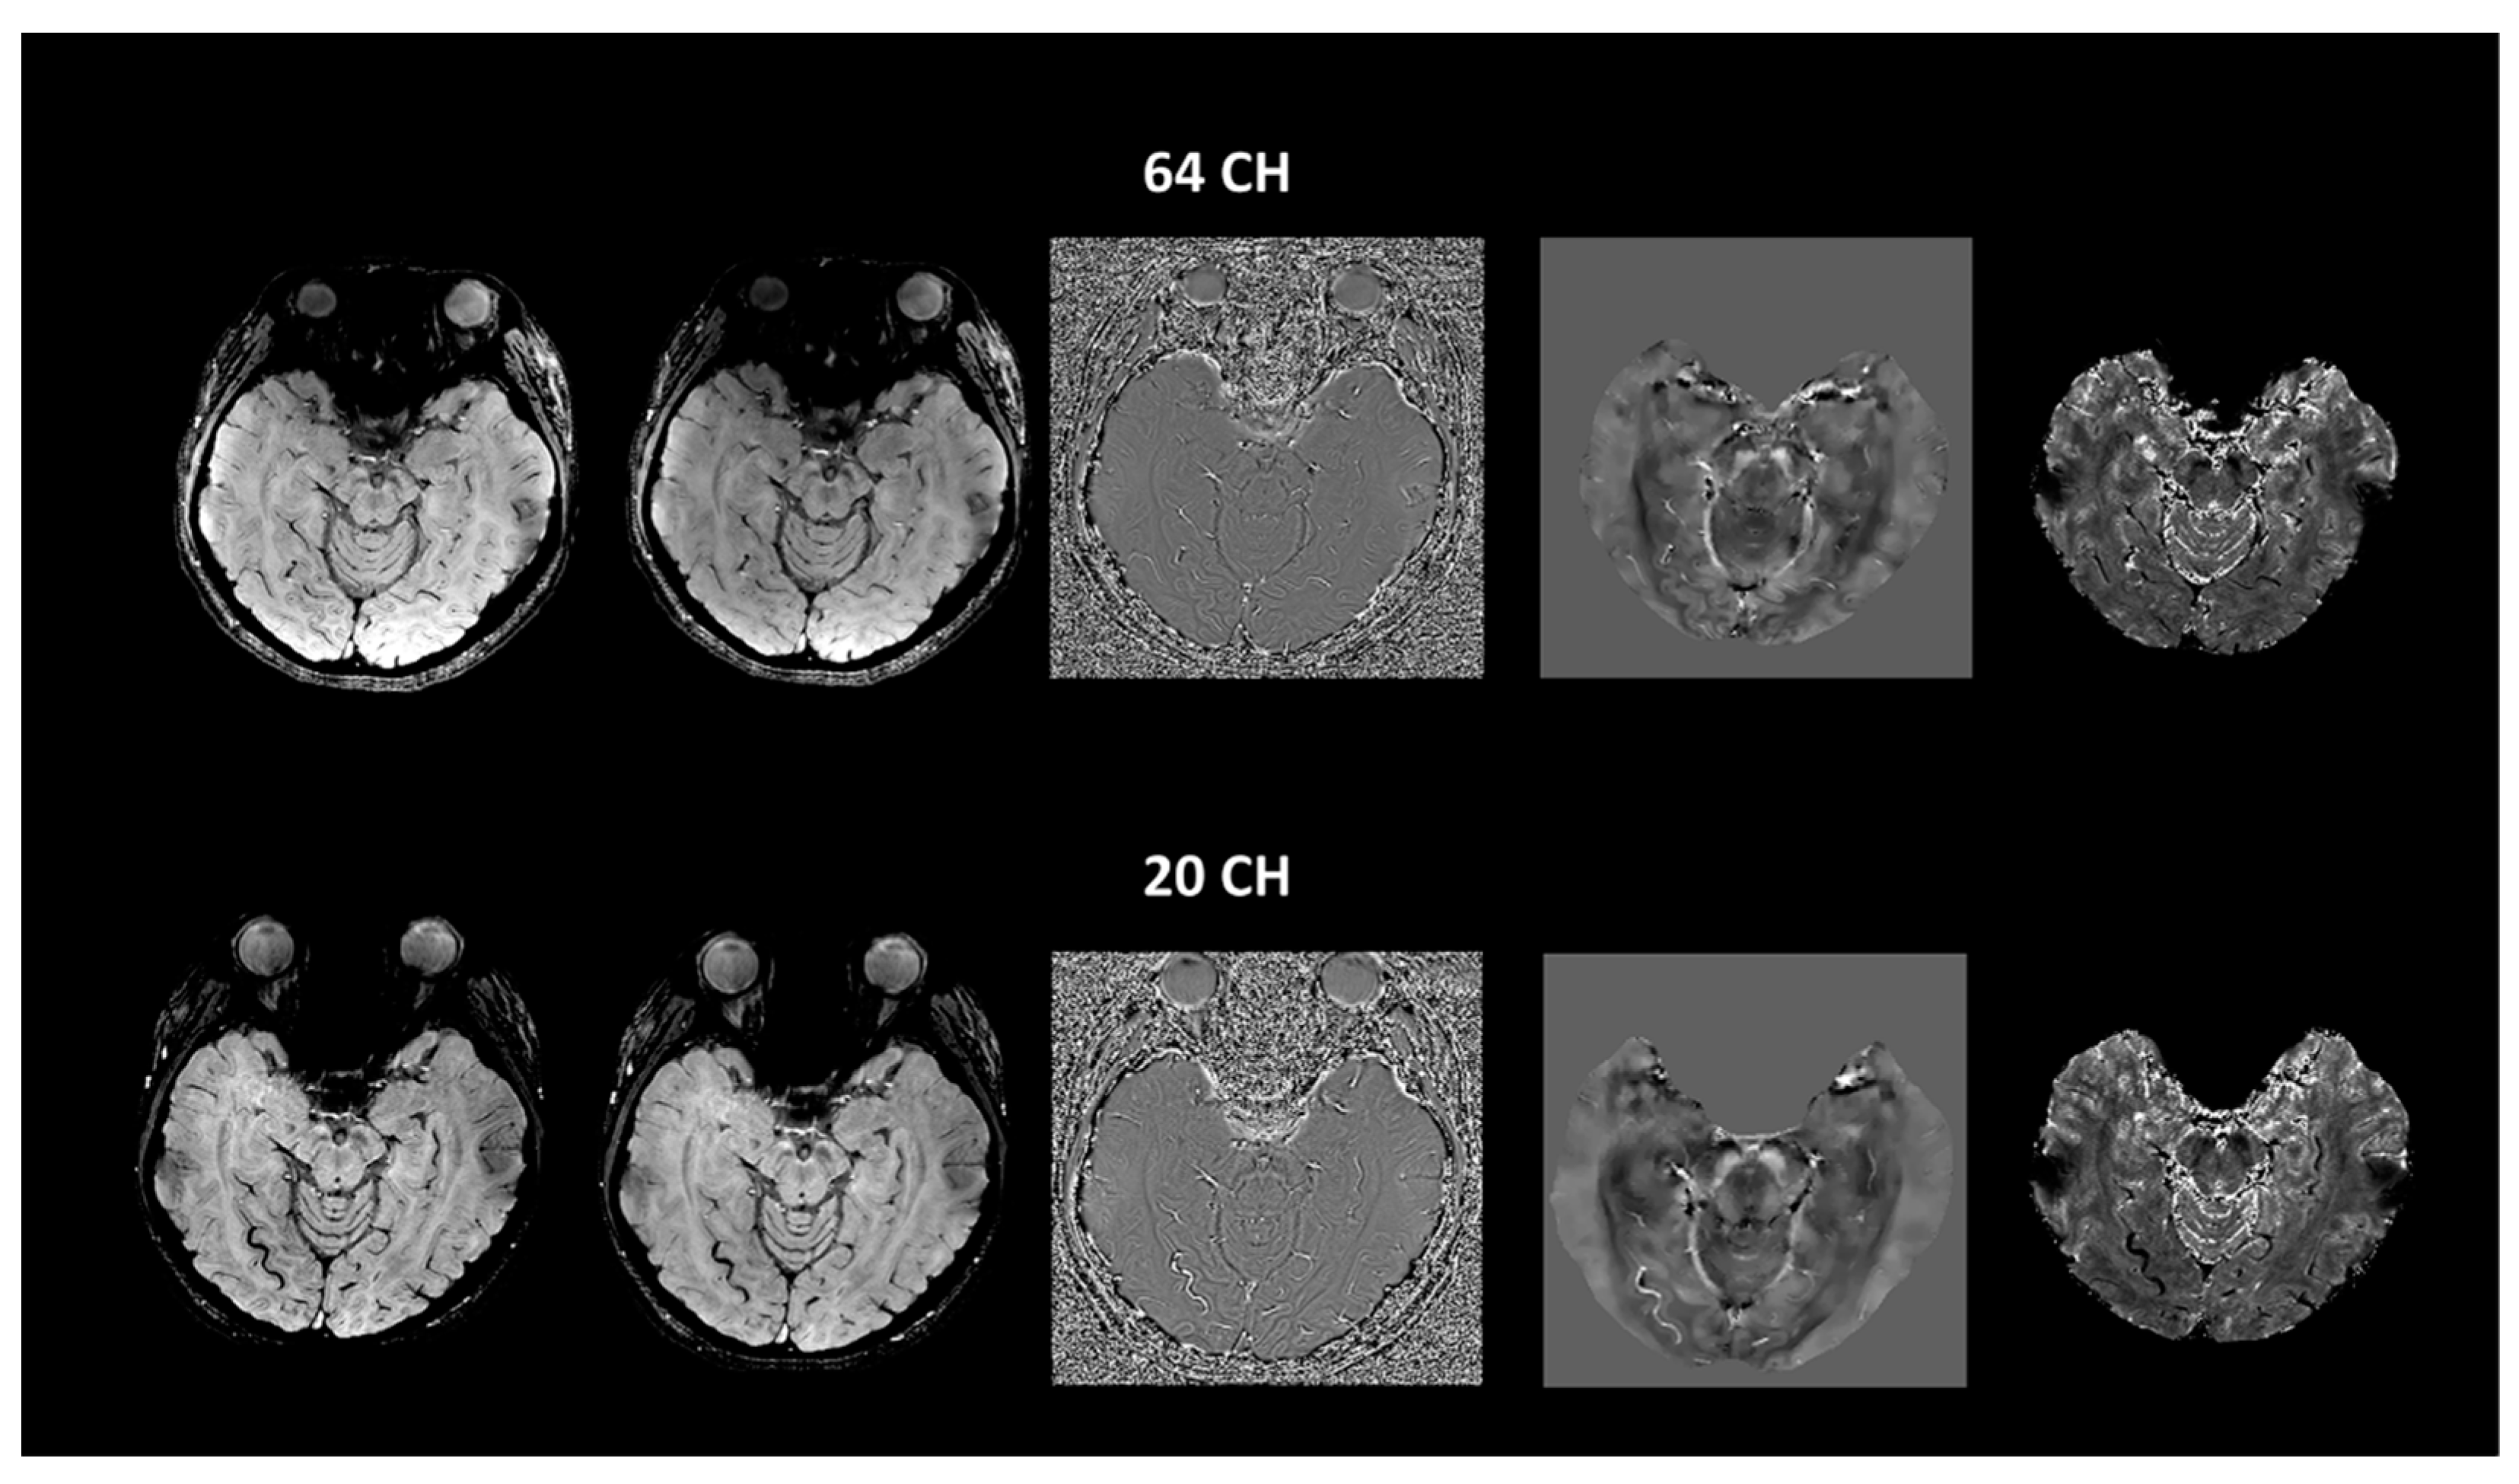

Evaluation of the Swallow-Tail Sign and Correlations of Neuromelanin Signal with Susceptibility and Relaxations

2.2. Imaging Protocols

2.3. Imaging Data Analyses